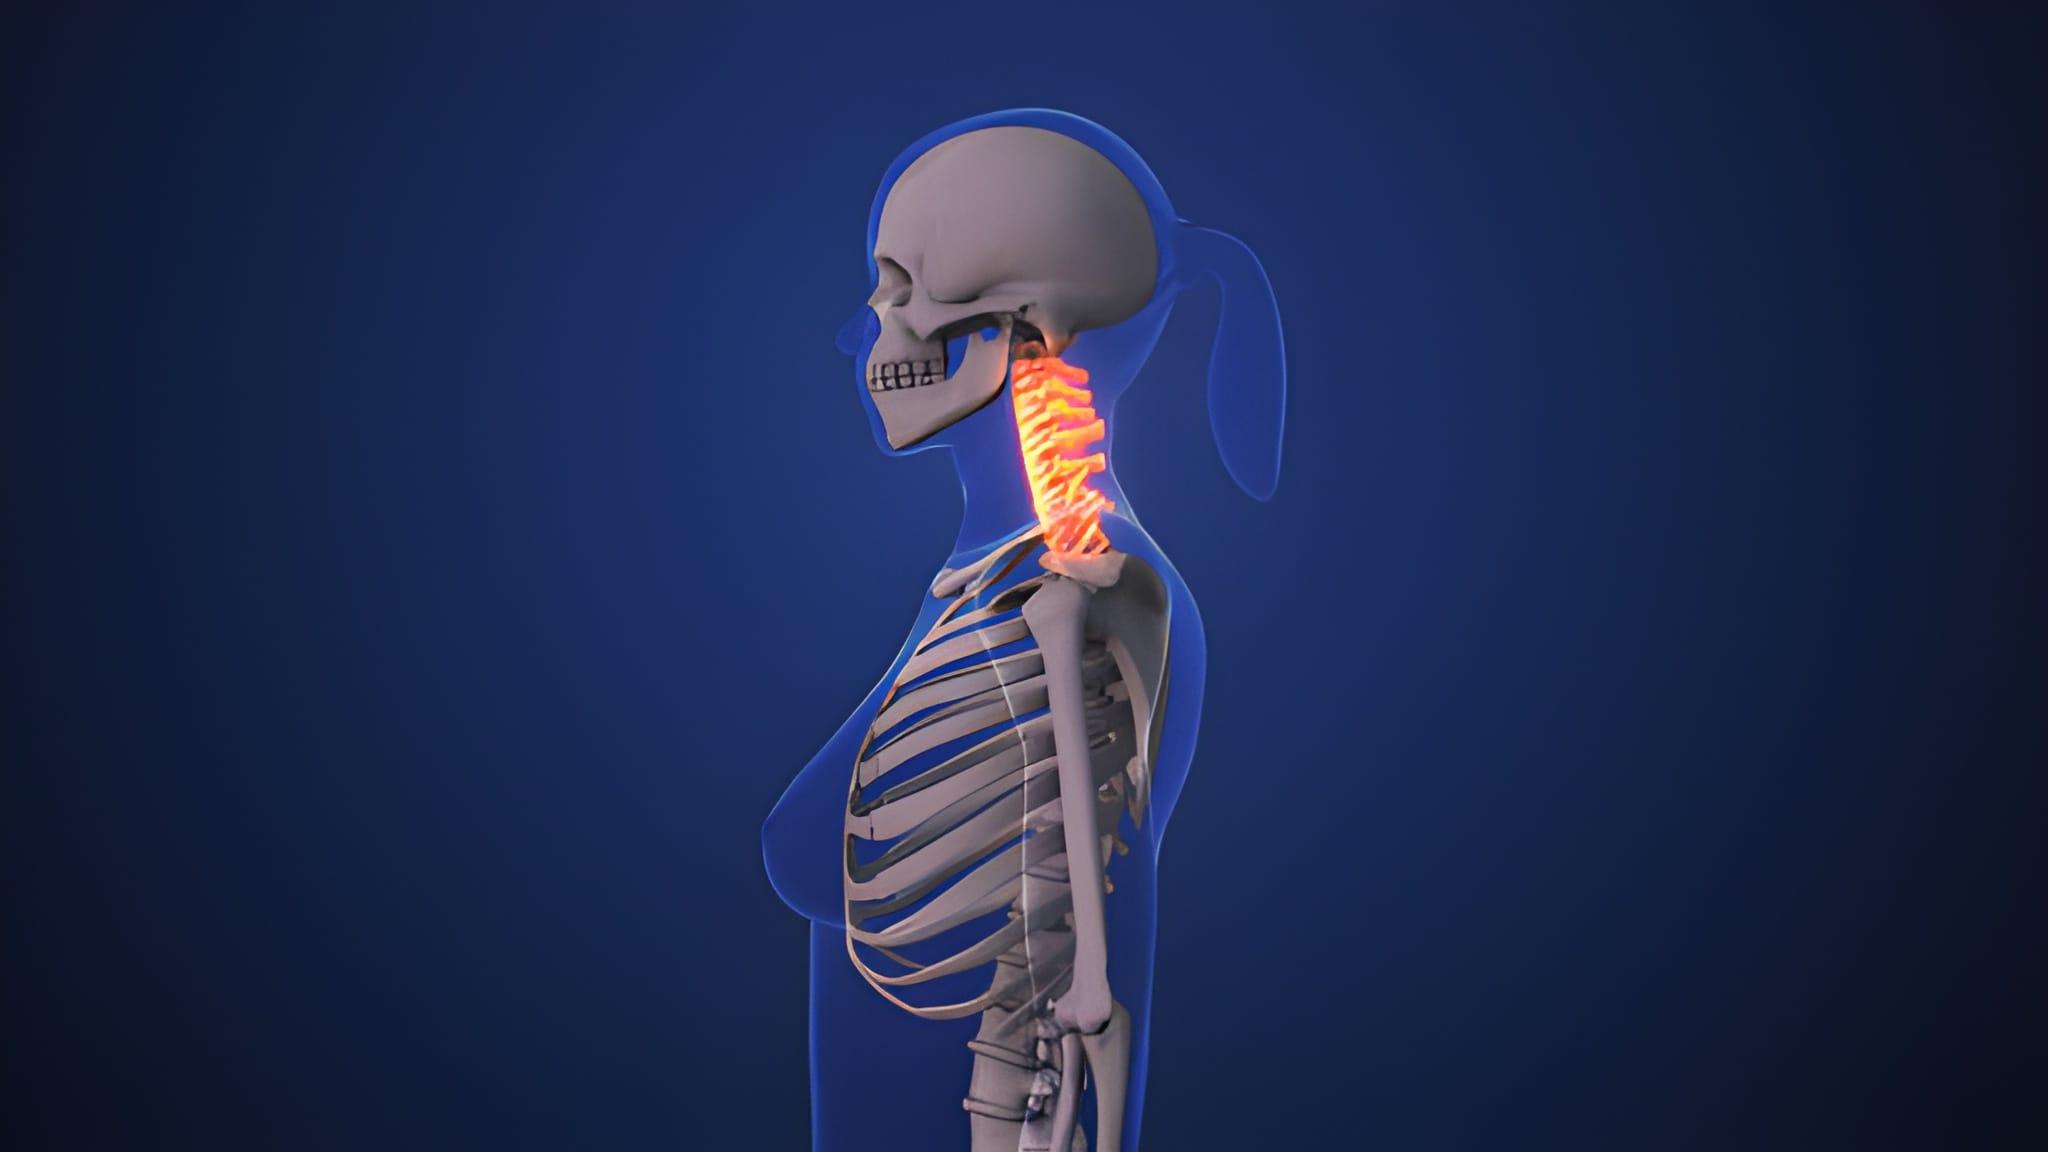

Spinal trauma can affect bones, discs, ligaments, and the spinal cord itself, often resulting in pain, instability, or loss of neurological function. Early and effective stabilization is essential to limit secondary damage and preserve mobility. The Spinal Trauma Devices Mechanism is designed to maintain alignment and provide structural support while natural healing occurs. Because injuries differ significantly by location and severity, clinicians depend on a wide array of adaptable devices suitable for different regions of the spine and diverse patient anatomies.

At the heart of spinal trauma treatment are fixation systems engineered to withstand complex mechanical forces. Internal components such as screws, rods, plates, and cages work together to restore stability and load-bearing capacity. The development of lighter, stronger materials and imaging-compatible designs has elevated the effectiveness of Spinal Trauma Devices Medical devices, allowing surgeons to achieve precise placement while minimizing surgical disruption. These advances support modern clinical goals of shorter hospital stays and faster rehabilitation.